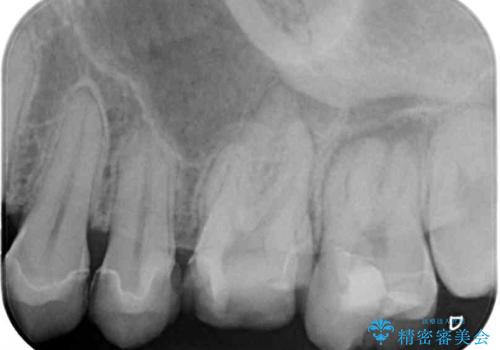

診査したところ、根尖部の病変は大きいものの、抜歯が必要とは決して思えず、まずは根管治療を行うべきと判断しました。

2,3回の処置後には来院時に感じていた痛みはなくなり、根管治療から半年後にはレントゲンでの根尖部病変も消失していました。